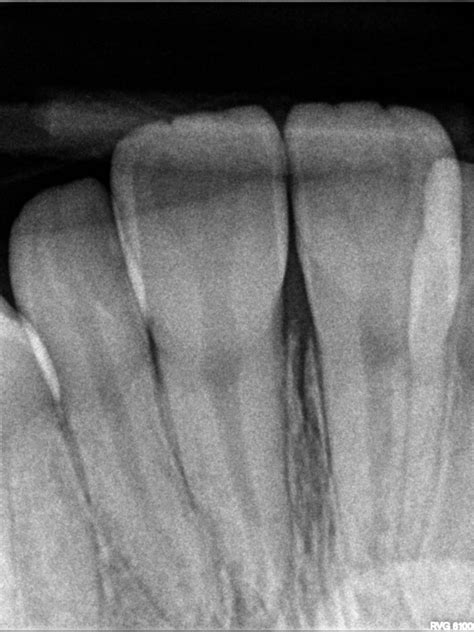

When you visit your dentist for a toothache or a routine check-up, they may recommend a specific type of dental imaging to get a clearer picture of your oral health. Among the various diagnostic tools available in modern dentistry, the Periapical X Ray stands out as an essential imaging technique. Unlike broader panoramic X-rays that capture the entire jaw, a periapical image focuses on one or two specific teeth, providing an incredibly detailed view of the tooth from the crown down to the very tip of the root and the surrounding bone structure. Understanding what this procedure entails can help alleviate any anxiety you might feel about your upcoming dental appointment.

A Periapical X Ray, often referred to simply as a "PA," is a close-up, high-resolution diagnostic image. The term "periapical" literally translates to "around the apex," with the apex being the tip of the tooth root. This specific type of X-ray is designed to show the entirety of the tooth—from the biting surface (crown) down to the root end—as well as the surrounding supporting bone.

Because it offers such fine detail, dentists utilize this scan to diagnose specific problems that might be missed by broader imaging methods. Whether you are experiencing localized pain, sensitivity, or require a procedure that demands precision, this X-ray is often the first step toward an accurate diagnosis.